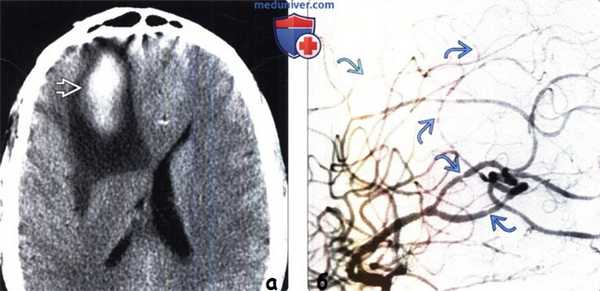

(а) Бесконтрастная КТ, аксиальный срез: у мужчины 42 лет с рецидивирующими высокоинтенсивными головными болями в анамнезе и длительным анамнезом злоупотребления амфетамина в правой лобной доле определяется гиперденснаязона с перифокальным отеком, представляющая собой паренхиматозное кровоизлияние.

(б) ЦСА правой внутренней сонной артерии, боковая проекция: определяется неравномерность просвета и вид типа «нити бусин» ветвей СМА и ПМА среднего и малого калибра. Данные изменения согласуются с лекарственно-индуцированным васкулитом.

• Ангиография больших полушарий может выявлять неравномерность срединных внутричерепных сосудов, вызванный амфетамином васкулит